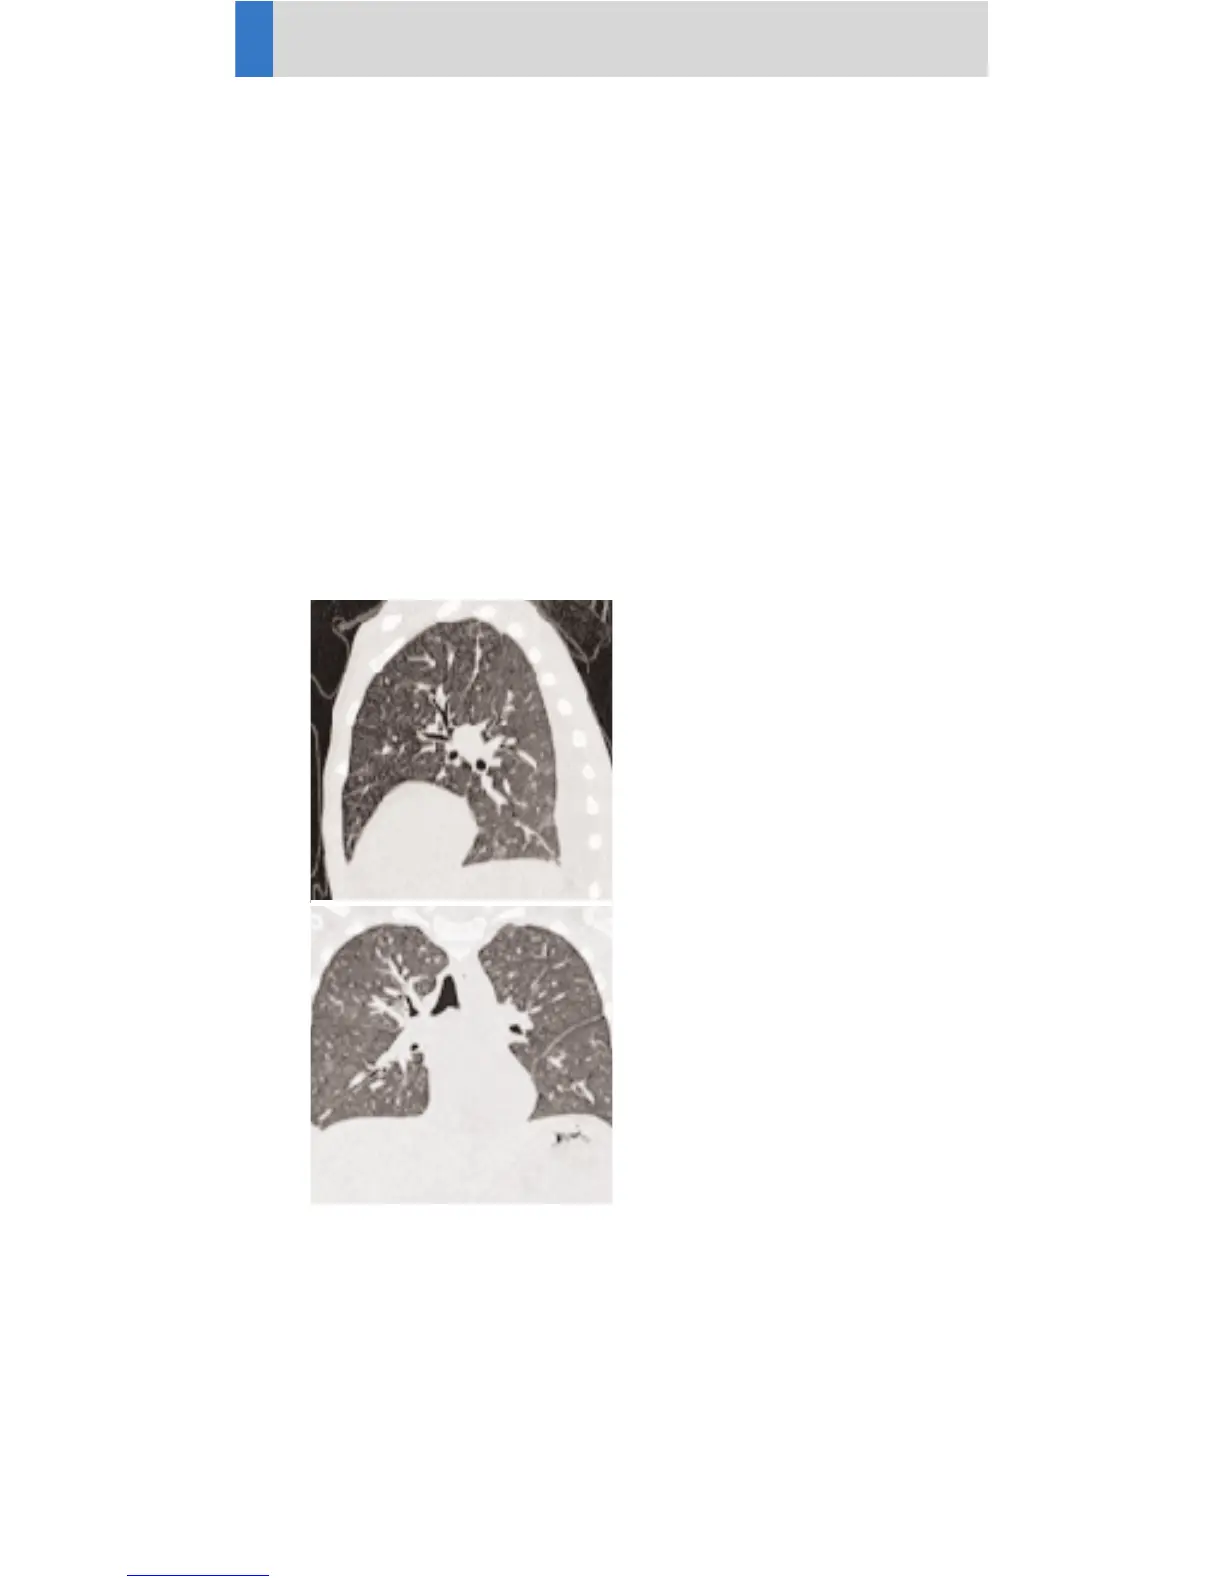

ThoraxCombi06s

Indications:

Combining thin slice lung and routine thorax studies

with one spiral scan. E. g. thorax studies in general

and interstitial changes in the lungs. There are two

recon jobs predefined. The first one, with 3 mm slice

thickness, for the mediastinum, the second recon-

struction, with 1.25 mm slice thickness, for the lung,

using a 0.6 sec. rotation time.

A range of 15 cm will be covered in 11.2 sec.